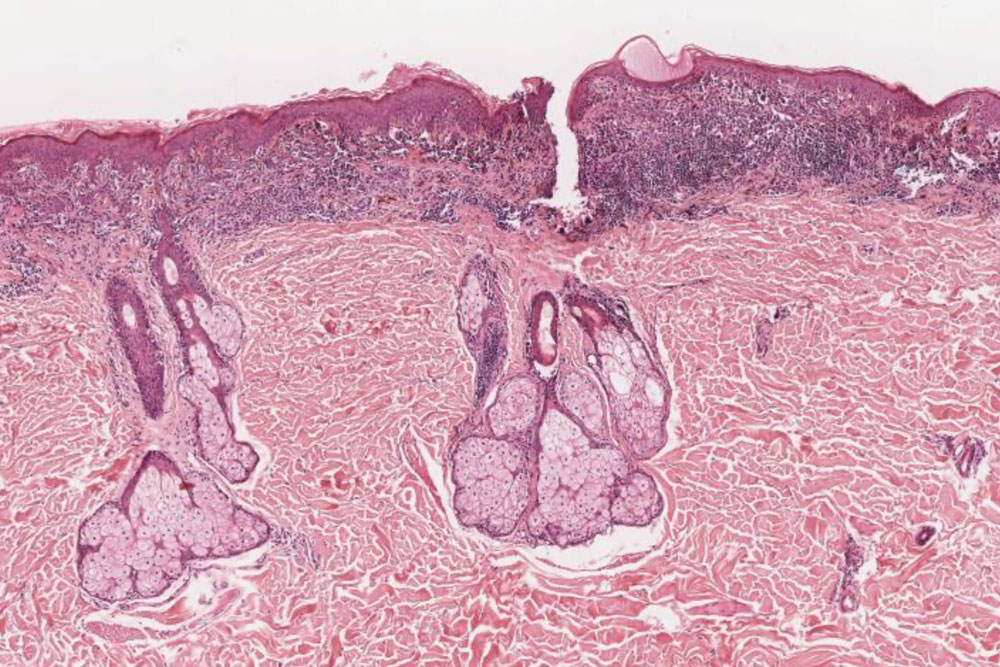

Diagnostik von Hauttumoren inklusive Morphometrie

Melanomdiagnostik nach Leitlinien

Abklärung von entzündlichen Dermatosen und Vaskulitiden